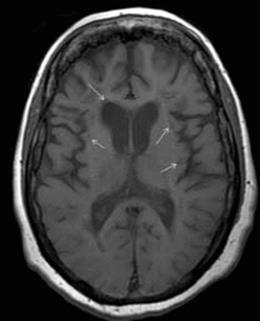

Figure 22.4 T1 black holes (arrows) in a patient with advanced MS. Note also the presence of cerebral atrophy.

T1 black holes

The meaning of these hypointense (dark) signals on T1-weighted images is not entirely clear. Although many T1 black holes revert to an isointense signal over time, it is likely that those that persist reflect severe demyelination and irreversible axon loss (Figure 22.4).4